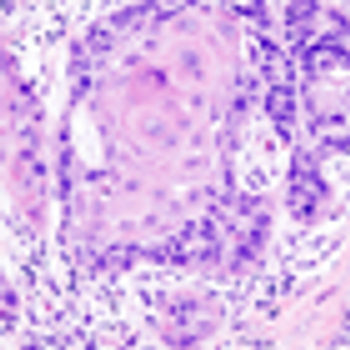

High-risk HPVs may be present more frequently than previously estimated in a variety of head and neck cancers, supporting the use of a combination of methods to detect high-risk strains.